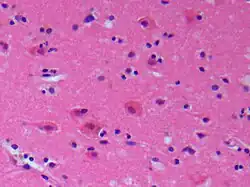

Das Gehirngewebe wird wie andere Gewebe über das Blut mit Energiesubstraten und Sauerstoff versorgt. Das Gehirn bezieht die Energie hauptsächlich aus dem Abbau von Glukose. Dabei werden über 95 Prozent der Glukose über Glykolyse und die Atmungskette abgebaut, wofür Sauerstoff benötigt wird (aerober Stoffwechsel). Bei Sauerstoffmangel wird die Glukose zu größeren Anteilen über den anaeroben Stoffwechselweg (Glykolyse und Milchsäuregärung) abgebaut. Beim anaeroben Stoffwechselweg ist die Energieausbeute wesentlich geringer. Daher und aufgrund nur geringer Glukose- und Sauerstoffvorräte kann eine Unterbrechung der Substratzufuhr nur kurzzeitig toleriert werden. Bei kompletter Unterbrechung der Sauerstoffzufuhr ist der Sauerstoff in der zellreichen grauen Substanz bereits nach 68 Sekunden verbraucht, die Glukose nach 34 Minuten. Nach 4 bis 5 Minuten sterben erste Nervenzellen („es treten Nekrosen auf“).[4]

Unterschreitet der zerebrale Blutfluss bzw. die Energiezufuhr die so genannte Funktionsschwelle, stellen die Hirnzellen ihre aktive Funktion zunächst reversibel ein. Es kommt zur Ischämie. Dieser Zustand kann jedoch nur eine bestimmte Zeit aufrechterhalten werden. Bei länger anhaltender Ischämie entsteht ein Infarkt, da die Zellstruktur nicht länger erhalten werden kann. Sinkt der zerebrale Blutfluss bzw. die Energiezufuhr weiter und unter die so genannte Infarktschwelle, werden die Hirnzellen ebenfalls irreversibel geschädigt und sterben ab, so dass ein Infarkt entsteht.